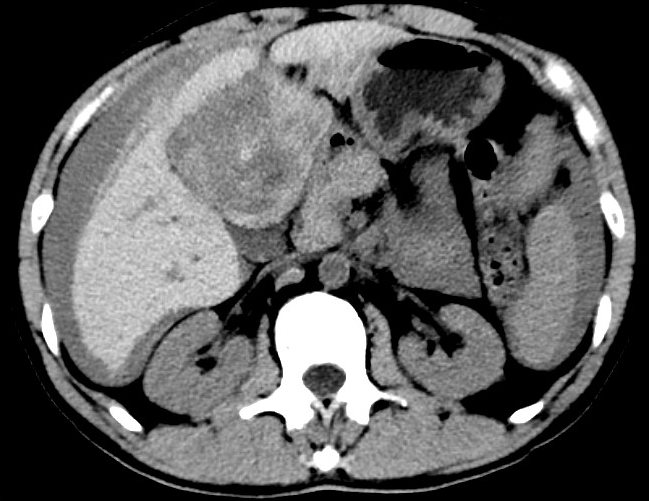

放下電話(huà)的白葦急赴消內(nèi)三搶救室會(huì)診,經(jīng)仔細(xì)查體、對(duì)患者腹部CT進(jìn)行詳細(xì)閱片、綜合評(píng)估患者后,考慮患者是肝占位破裂出血。患者病情十分緊急、一刻也不容耽誤,需立刻急診行肝動(dòng)脈造影 栓塞術(shù)進(jìn)行止血治療,在與患者家屬溝通后,立即通知消化介入室準(zhǔn)備急診手術(shù)。

入手術(shù)室時(shí),患者神志迷糊,口唇干燥、重度貧血貌,心電監(jiān)護(hù)提示:心率140-160次/分,血壓70/43mmHg,這是失血性休克的表現(xiàn)!白葦快速建立靜脈通道緊急給予輸血,升壓,止血等液,立即給予肝動(dòng)脈造影,術(shù)中發(fā)現(xiàn)肝左葉疑似腫瘤病灶、病灶周?chē)芊种в性煊皠┩庖?,考慮血管破裂出血,迅速給予栓塞微球進(jìn)行肝動(dòng)脈栓塞。整個(gè)手術(shù)過(guò)程不足20分鐘,術(shù)后即刻患者心率降至100-110次/分、血壓升至90/60mmHg。

術(shù)后給予積極抗炎,止血,保肝、利尿等對(duì)癥治療,復(fù)查血常規(guī)提示活動(dòng)性出血停止后,在超聲引導(dǎo)下行腹腔穿刺引流術(shù),術(shù)后3天共引流出血性腹水約4000ml?;颊呓?jīng)復(fù)查各項(xiàng)指標(biāo)均趨于正常,復(fù)查CT提示腹腔積血已基本吸收,患者康復(fù)出院。